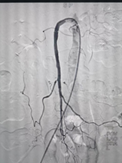

术中取栓前后肠系膜上动脉造影对比

经过介入手术,患者堵塞的肠系膜上动脉即时完全开通,且患者腹部疼痛症状明显改善。